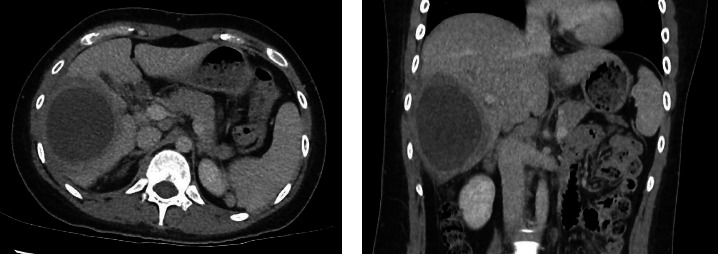

A liver abscess can be due to several different microbiological aetiologies. While pyogenic liver abscess is most frequently encountered, amoebic liver abscess and hydatid cyst caused by the parasites, Entamoeba histolytica and Echinococcus granulosus, respectively, should be considered whenever there is epidemiological exposure. As parasitic infections are now rarely seen in clinical practice in developed countries with improvement in sanitation, lack of clinical experience in managing amoebic liver abscesses and overlapping clinical and imaging features between amoebic and pyogenic liver abscesses may lead to delay in diagnosis. In particular, although amoebic liver abscesses respond well to treatment if diagnosed early, they can progress and rupture with high mortality if treatment is delayed. Hence, early diagnosis and prompt initiation of antimicrobials are crucial to prevent complications and death. This case report highlights a case of a very large 21 cm ALA in a young lady to illustrate the challenges faced during diagnostic evaluation.

Abstract Image